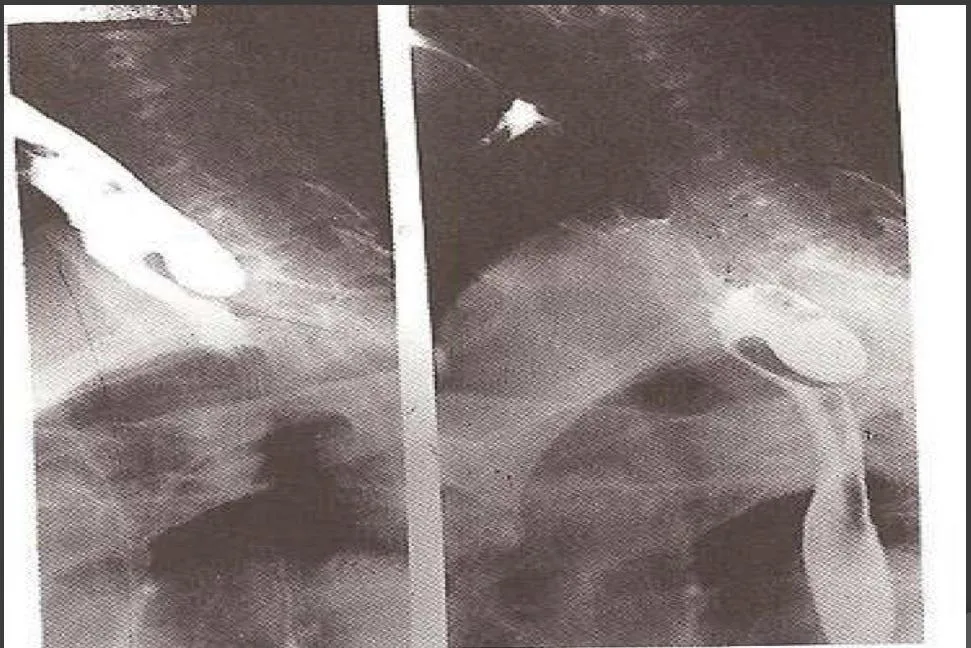

QRetropharyngeal Abscess

- Question: A 6- year- old child presented with stridor, odynophagia and fever. on examination there was bulge in the posterior pharyngeal wall, lateral X-ray shown in the picture.

- Answer:

- A- What is the most likely diagnosis?

- Retropharyngeal abscess

- B- What is the best management for this condition?

- Intra oral drainage & incision, I.V antibiotics, Airway Management